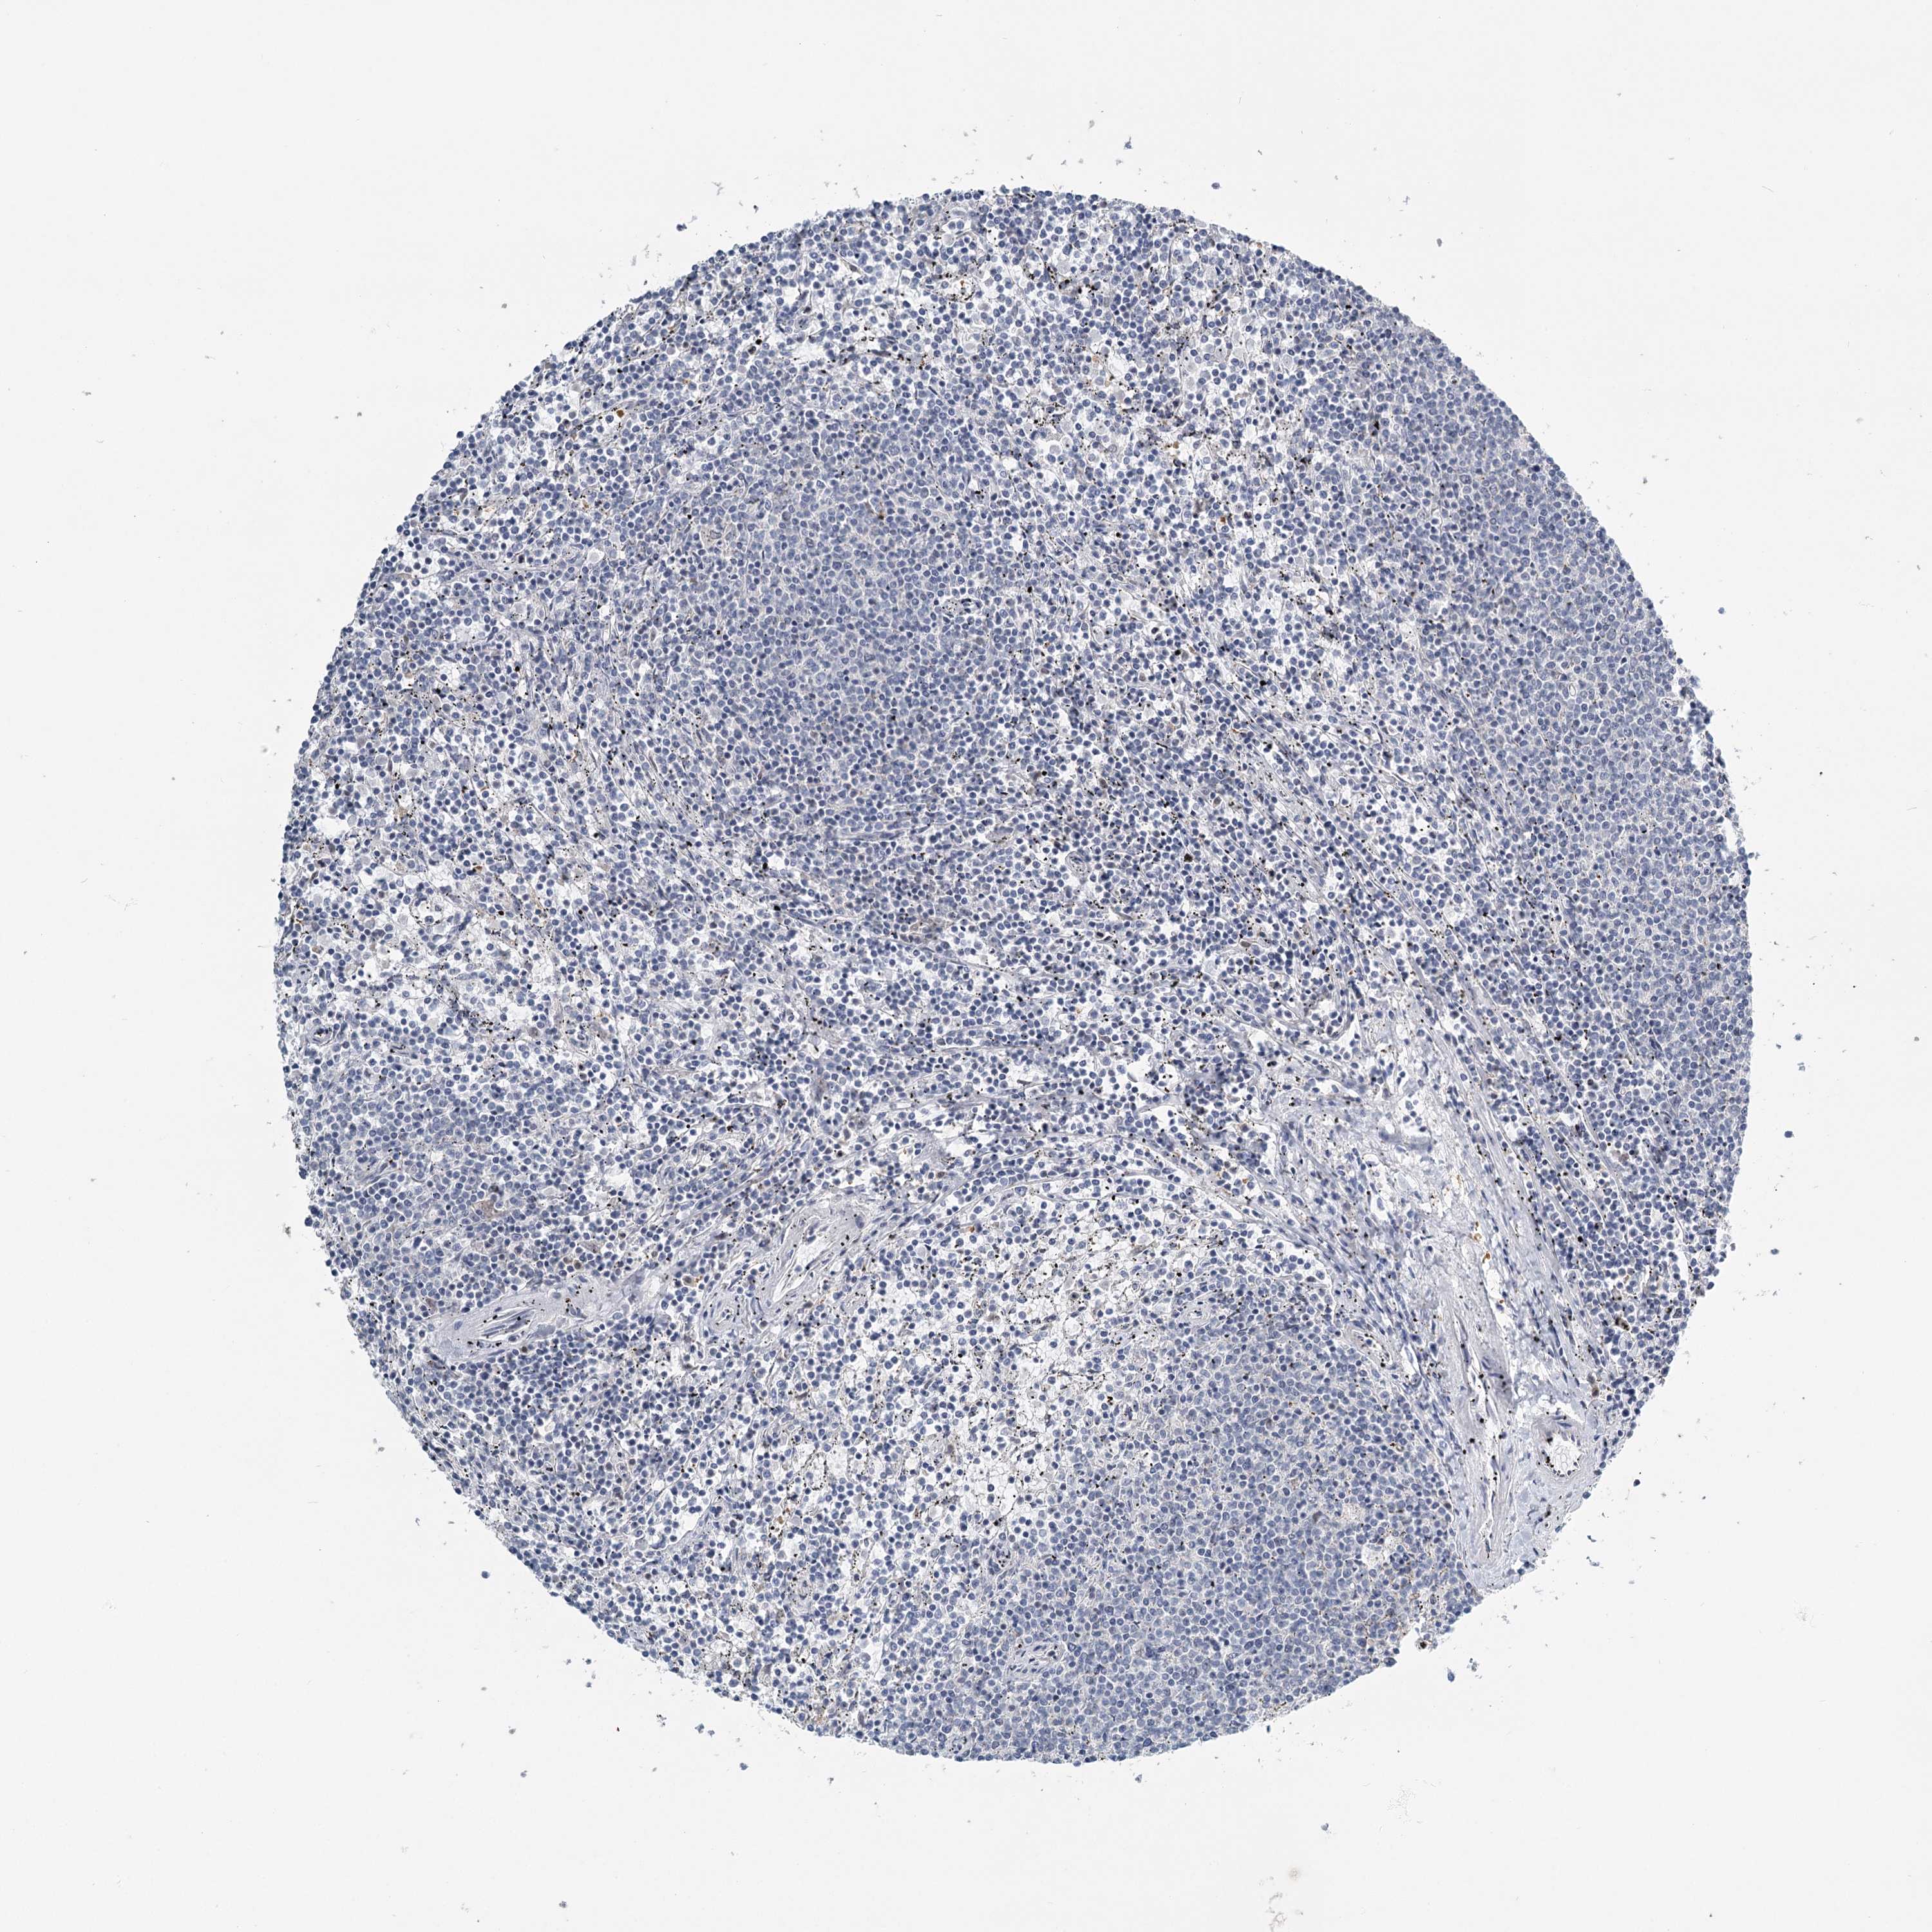

LYMPHOMA - Protein expressioni

A mouse-over function shows sample information and annotation data. Click on an image to view it in a full screen mode. Samples can be filtered based on level of antibody staining by selecting one or several of the following categories: high, medium, low and not detected. The assay and annotation is described here.

Each image is clickable and will lead to virtual microscopy that enables deeper exploration of all samples and also displays staining intensity scores, fraction scores and subcellular localization as well as patient and tissue information for each sample.

Antibody HPA023187

Antibody CAB034226

Staining

High

Medium

Low

Not detected

Intensity

Strong

Moderate

Weak

Negative

Quantity

>75%

75%-25%

<25%

None

Location

Nuclear

Cytoplasmic/membranous

Cytoplasmic/membranous,nuclear

Hodgkin's disease, NOS

Malignant lymphoma, non-Hodgkin's type, High grade

Malignant lymphoma, non-Hodgkin's type, Low grade